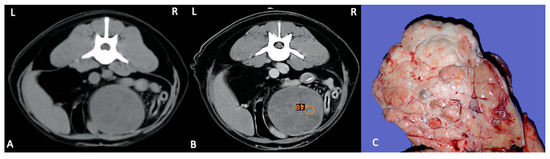

Imaging of Testicular Tumours